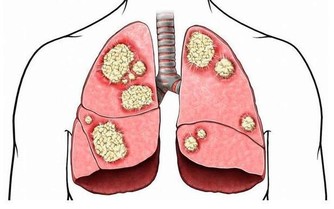

膀胱經預防和主治的疾病:呼吸系統:感冒、發燒、哮喘、肺炎;